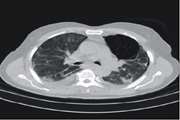

Clinical and chest CT features as a predictive tool for COVID 19 clinical progress: introducing a novel semi quantitative scoring system Jul 9 2024 - 07:52

Proven Aspergillus flavus pulmonary aspergillosis in a COVID-19 patient: A case report and review of the literature Jul 8 2024 - 11:26

Factors Predicting Outcome in Intensive Care Unit Admitted COVID 19 Patients: Using Clinical, Laboratory, and Radiologic Characteristics Jul 8 2024 - 11:22

COVID 19: Unilateral Involvement of Transplanted Lung, Sparing Contralateral Fibrotic Lung Jul 8 2024 - 11:01